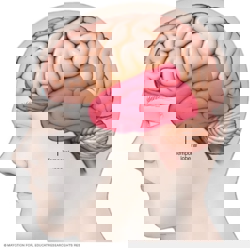

Location of temporal lobe

The temporal lobe is located along each side of the brain.